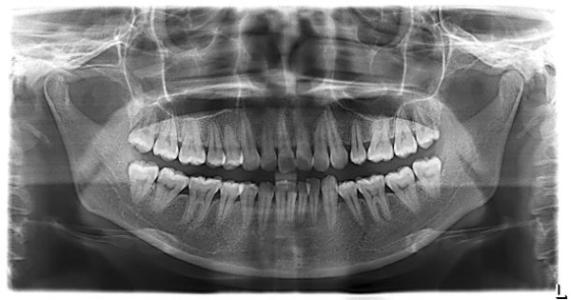

牙齿由两部分组成,牙冠和牙根。牙冠分为牙釉质,牙本质和牙髓。除了在外层上有一点牙釉质外,牙齿上里面有问题你是看不到的。因此,为了充分了解牙齿问题,需要拍牙片进行观察。

01拍摄胶片:就像拥有驾照一样,但是为了科学诊断,避免误诊,避免盲目手术以及避免那些不必要的结果,因此普通的正规牙科诊所将要求患者在治疗前先进行X射线检查,提高诊断的准确性和成功率。

如智齿拔牙,充填,根管治疗(牙痛),牙周疾病,种植牙,正畸等都需要拍摄。